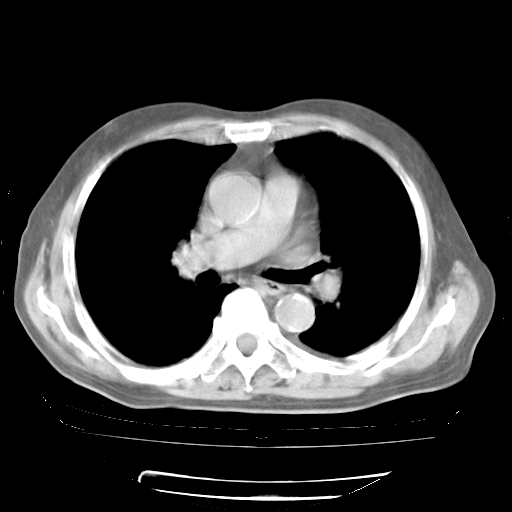

今天部分检查

轻微咳嗽,无痰,(体温正常时)R20次/分,P75次/分,双肺底、腋下可闻及少量捻发音。下肢轻度浮肿。

ECG:右心室增大

心脏超声检查:无右心室增大。